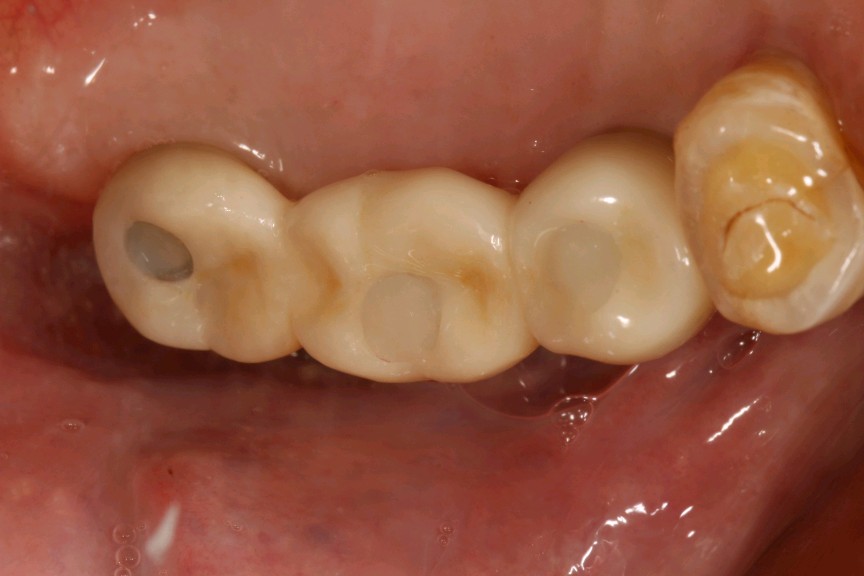

患者男,五十岁,右上后牙缺失一年。治疗计划拔出后种植修复。综合考虑患者自愿选择欧美hiossen种植体。最终15植入hiossen种植体4.5*11.5mm;16、17植入hiossen种植体5.0*10mm。二期三期如期进行。余近日戴牙。